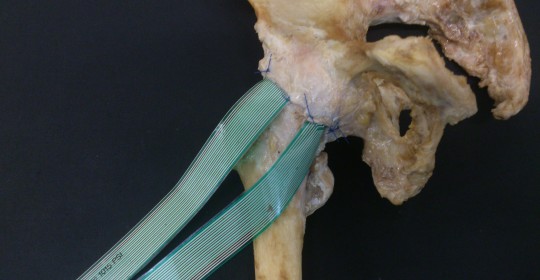

Tesis Doctoral

Estudio de presión articular de cadera, Influencia de la lesión del rodete acetabular.

El estudio muestra cómo la reparación del rodete acetabular logra restaurar las presiones articulares previas a la lesión del mismo